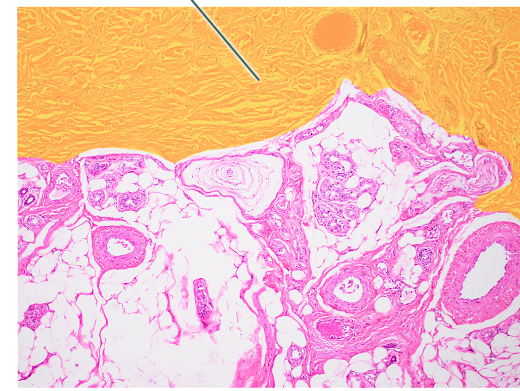

loose adipose connective tissue

loose areolar connective tissue

dense irregular connective tissue

location of areolar loose connective tissue

dermis

location of adipose loose connective tissue

location of dense irregular connective tissue